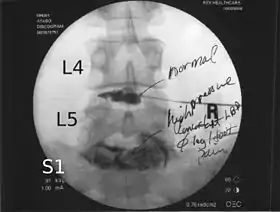

![]() Lumbar provocative discography showing a degenerated disc, L5-S1 with normal disc L4-L5 | |

Spinal MRI is the imaging of choice to investigate the spine and intervertebral discs.[1] Meanwhile, lumbar discography is used to demonstrate degeneration and herniation of lumbar intervertebral discs by injecting a dye into the nucleus pulposus of the discs. The procedure is also used to reproduce pain back pain for those who have such symptoms. Lumbar discography is also used to access the response of a subject to anaesthetic injection. Other uses include suspected discogenic pain without radicular sign (pain travelling to lower limbs along a dermatome) and confirmation of normal intervertebral discs above and below a site before spinal fusion.[1] However, evidence supporting the usefulness of lumbar discography in recognizing intervertebral disc problems is limited.[1] There is no role for cervical or thoracic discography in diagnosing disc pathologies at the cervical or thoracic regions.[1][2]